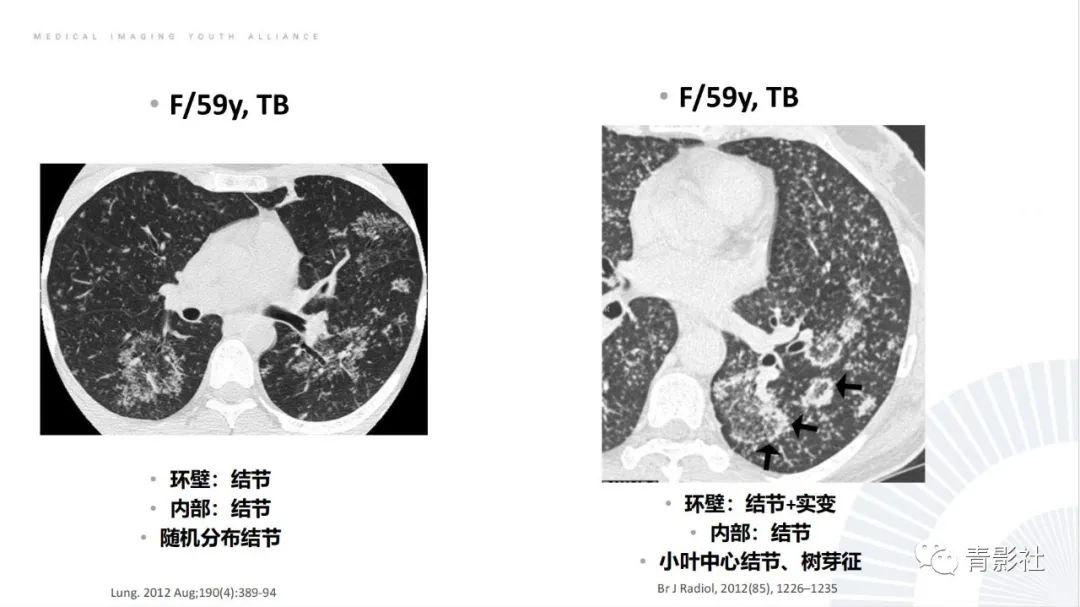

【PPT】肺部反晕征影像诊断思维-7